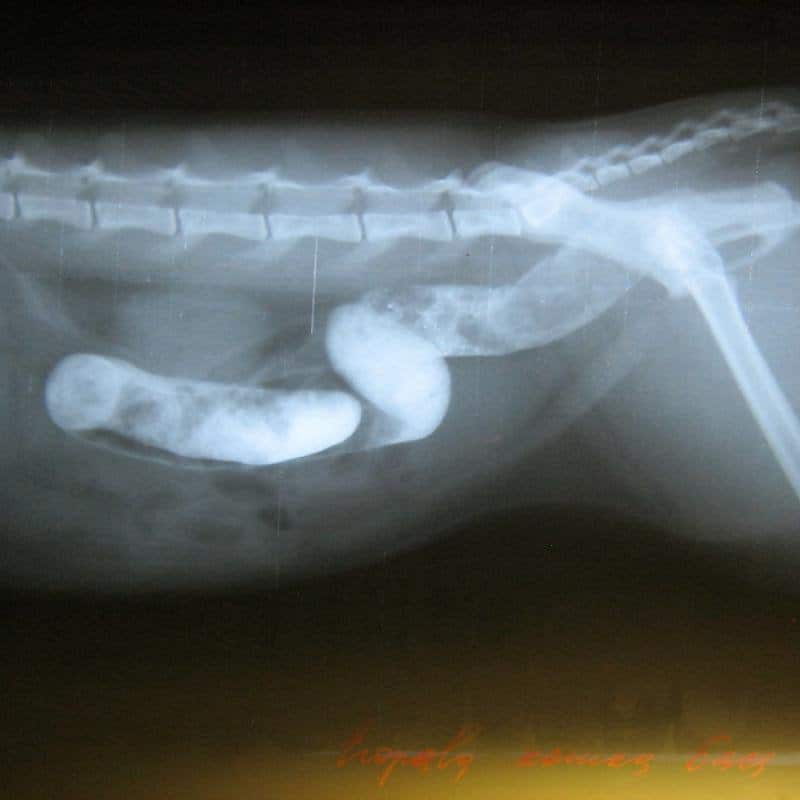

Рекомендации теста могут включать: - Рентгенограммы брюшной полости (рентгеновские снимки) — важный тест. К сожалению, не все инородные материалы видны на первоначальном рентгеновском снимке. Иногда рекомендуется добавление красителя, такого как барий, чтобы определить наличие инородного тела или непроходимости желудка.

Некоторые объекты легко увидеть с помощью рентгеновских лучей, а другие — нет. В этих случаях ваш ветеринар может назначить контрастное исследование, при котором ваш питомец должен проглотить барий, чтобы выделить объект в его пищеварительном тракте. Ваш ветеринар также может порекомендовать анализы крови и мочи, чтобы определить наличие других заболеваний, например панкреатита.